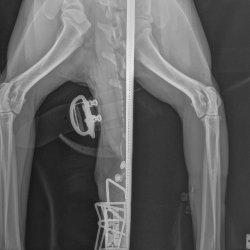

Příběhy Rocky s kulháním na pravou hrudní končetinu

Rocky s kulháním na pravou hrudní končetinu

Rocky je krasavec, se kterým se život nemazlil. Nejprve žil přivázaný u stromu, poté se čas změnil a strom se vystřídal řetěz v kotci. Žil ve vlastních výkalech, bez dostatku čerstvé vody a krmiva. Až po dlouhém nekonečném čase přišla záchrana, a to v podobě tet z Voříškova. Rocky k nim přišel na začátku tohoto roku celý pohublý, kulhající, se zažívacími potíži a s velkým strachem z cizích lidí.

Protože kulhání na pravou hrudní nožičku stále přetrvává, vzaly minulý týden Rockyho tety z Voříškova na vyšetření k panu doktoru.

RTG snímek Rocky